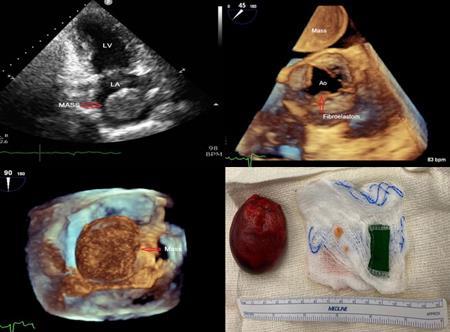

LARYNGEAL SYNOVIAL SARCOMA THAT METASTASIZED TO THE HEART

Christopher N. Matthews1 , Syed Farrukh Mustafa1 , Sidra Salman1 , Akshaya

Gopalakrishnan1, James Salonia1 , Deepika Misra1

To be presented at the American Society of Echocardiography Annual Scientific Sessions that will be held in National Harbor, Maryland, United States from June 23-26, 2023. 45

1Mount Sinai Morningside-West Hospitals, Icahn School of Medicine at Mount Sinai, New York, NY, United States

Presented at the American College of Cardiology (ACC) Annual Meeting that was held in New Orleans, Louisiana, United States from March 4-6, 2023.